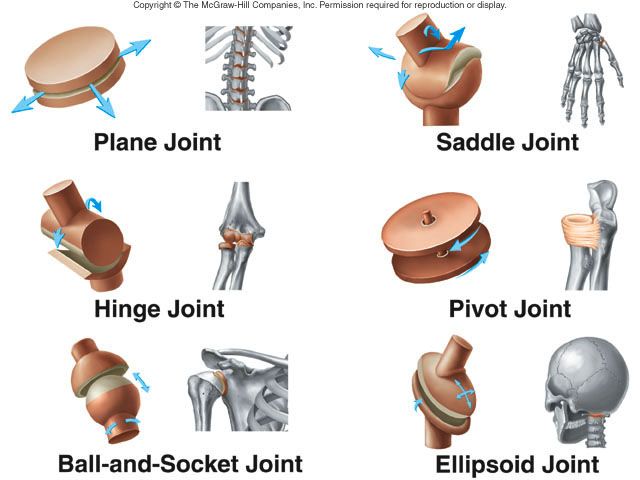

TOPIC: JOINTS

Movement in the bodies of humans is made possible by the joints in the body. The point where two bones meet is called a joint.

TYPES OF JOINTS

1. The Immovable Joints:

These joints do not allow for movement. These are:

(a) Ball and socket joint:

(b) Gliding joint:

These are found in the limbs. Ball and socket joints are in the shoulder and hip. They allow for movement in more than one plane.

2. The Moveable Joints:

(a) Hinge joint: this is a joint which allows for movement in only one plane/direction e.g. elbow joint.

Gliding joints allows the sliding, twisting or turning of one bone over another e.g. joints at the wrist.

Movement in the bodies of humans is made possible by the joints in the body. The point where two bones meet is called a joint.

TYPES OF JOINTS

1. The Immovable Joints:

These joints do not allow for movement. These are:

(a) Ball and socket joint:

(b) Gliding joint:

These are found in the limbs. Ball and socket joints are in the shoulder and hip. They allow for movement in more than one plane.

2. The Moveable Joints:

(a) Hinge joint: this is a joint which allows for movement in only one plane/direction e.g. elbow joint.

Gliding joints allows the sliding, twisting or turning of one bone over another e.g. joints at the wrist.